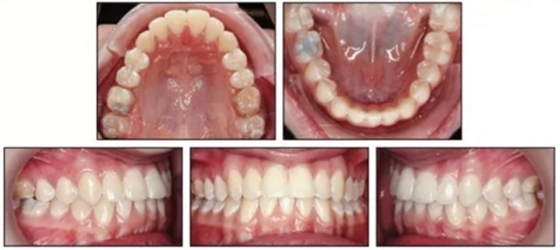

治療結(jié)束后,患者雙側(cè)達到安氏I類關(guān)系,正常的覆合覆蓋及接近理想的前牙軸傾度。頭側(cè)結(jié)果再次確認了通過上頜伸長安氏III已得到矯正,SNA從73.1°增大到78.1°(表1)。上頜前磨牙間寬度增加了約9mm。下頜MP-PP角減小了4.9°,面型接近中等面型。

患者繼續(xù)佩戴活動保持器,治療后13月隨訪提示其仍處于一個穩(wěn)定的咬合關(guān)系。(圖5)